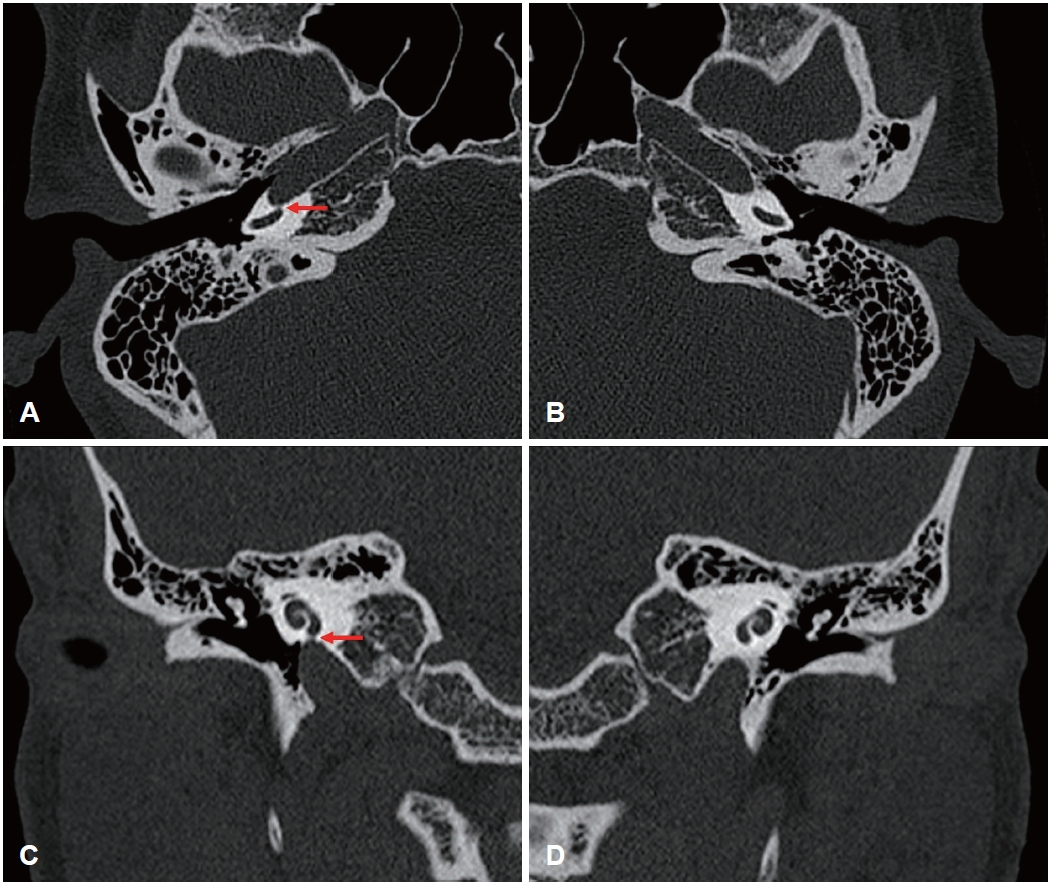

Carotid Artery-Cochlear Dehiscence Presenting With Pulsatile Tinnitus: A Case Report and Review of the Literature ( 440 times )

Ki Hun Jo, Jong Hyun Choi, Joo Yeon Kim, Jae Hwan Kwon

Received October 23, 2025     Accepted December 29, 2025     Published online February 10, 2026

DOI: https://doi.org/10.3342/kjorl-hns.2025.00521

[Epub ahead of print]

kjorl-hns-2025-00521f1.jpgkjorl-hns-2025-00521f2.jpg